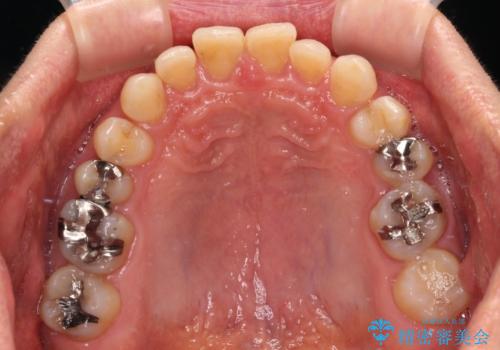

- 前歯のデコボコと隙間の空いた歯列を気にして来院された患者様です。

下顎前歯が隠れるほどのディープバイトにより、強い咬合力と突き上げで上顎歯列に隙間が空いている状態でした。

手前に傾斜している奥歯をワイヤー装置で立ち上がらせ、咬み合わせの高さを挙上することで突き上げを解消し、空隙歯列を改善していくこととしました。